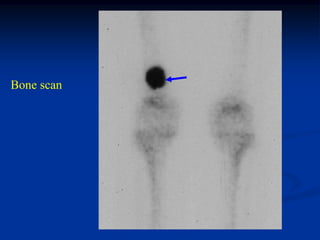

Bone scan